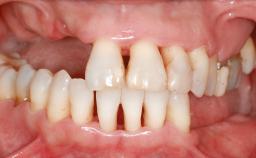

An 80-year-old female patient was referred to clinic for rehabilitation of her dentition. The patient’s medical history revealed no significant findings that would preclude routine dental and oral surgical procedures. She reported no drug allergies and was currently taking no prescription medications.

Her chief complaint was her inability to masticate efficiently due to the recent loss of her mandibular second premolars and first molars bilaterally. She expressed a desire for fixed prostheses in the shortest possible time due to her advanced age, requesting that replacement teeth should look as natural as possible. She was otherwise comfortable and not experiencing any symptoms from her teeth.

Prosthesis Type FDP

SAC Level Straightforward

Defining Characteristics Up to three missing teeth to be replaced with an implant-borne restoration or restorations